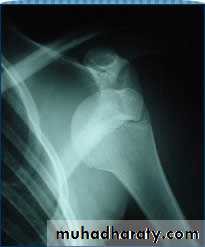

Anterior dislocation of the shoulder

It caused by fall on out stretched hand , the head of the humerus driven foreword tearing the capsule or avulsing the glenoid labrum, and settled under the clavicle in the infraclavicular fossa .Clinically : history of trauma , sever pain , the patient support his arm with the opposite hand and resist any kind of examination .

On examination : there is loss of normal contour of the affected shoulder , visible or palpable boney mass below the clavicle .

X –ray :

1- antero-posterior view show the head of the humerus out of the glenoid and located usually below of the clavicle or the coracoid process .2- axillary view is very helpful also .

Anterior shoulder dislocation